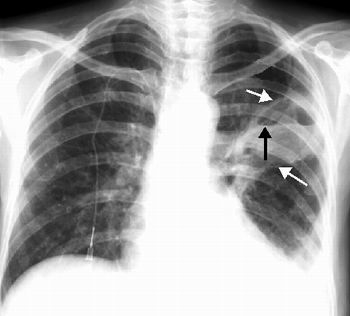

c.Röntgen filmi çekildiği zaman, filmde hastalığın özellikleri ve apse boşluğu da belirli bir şekilde görülür.